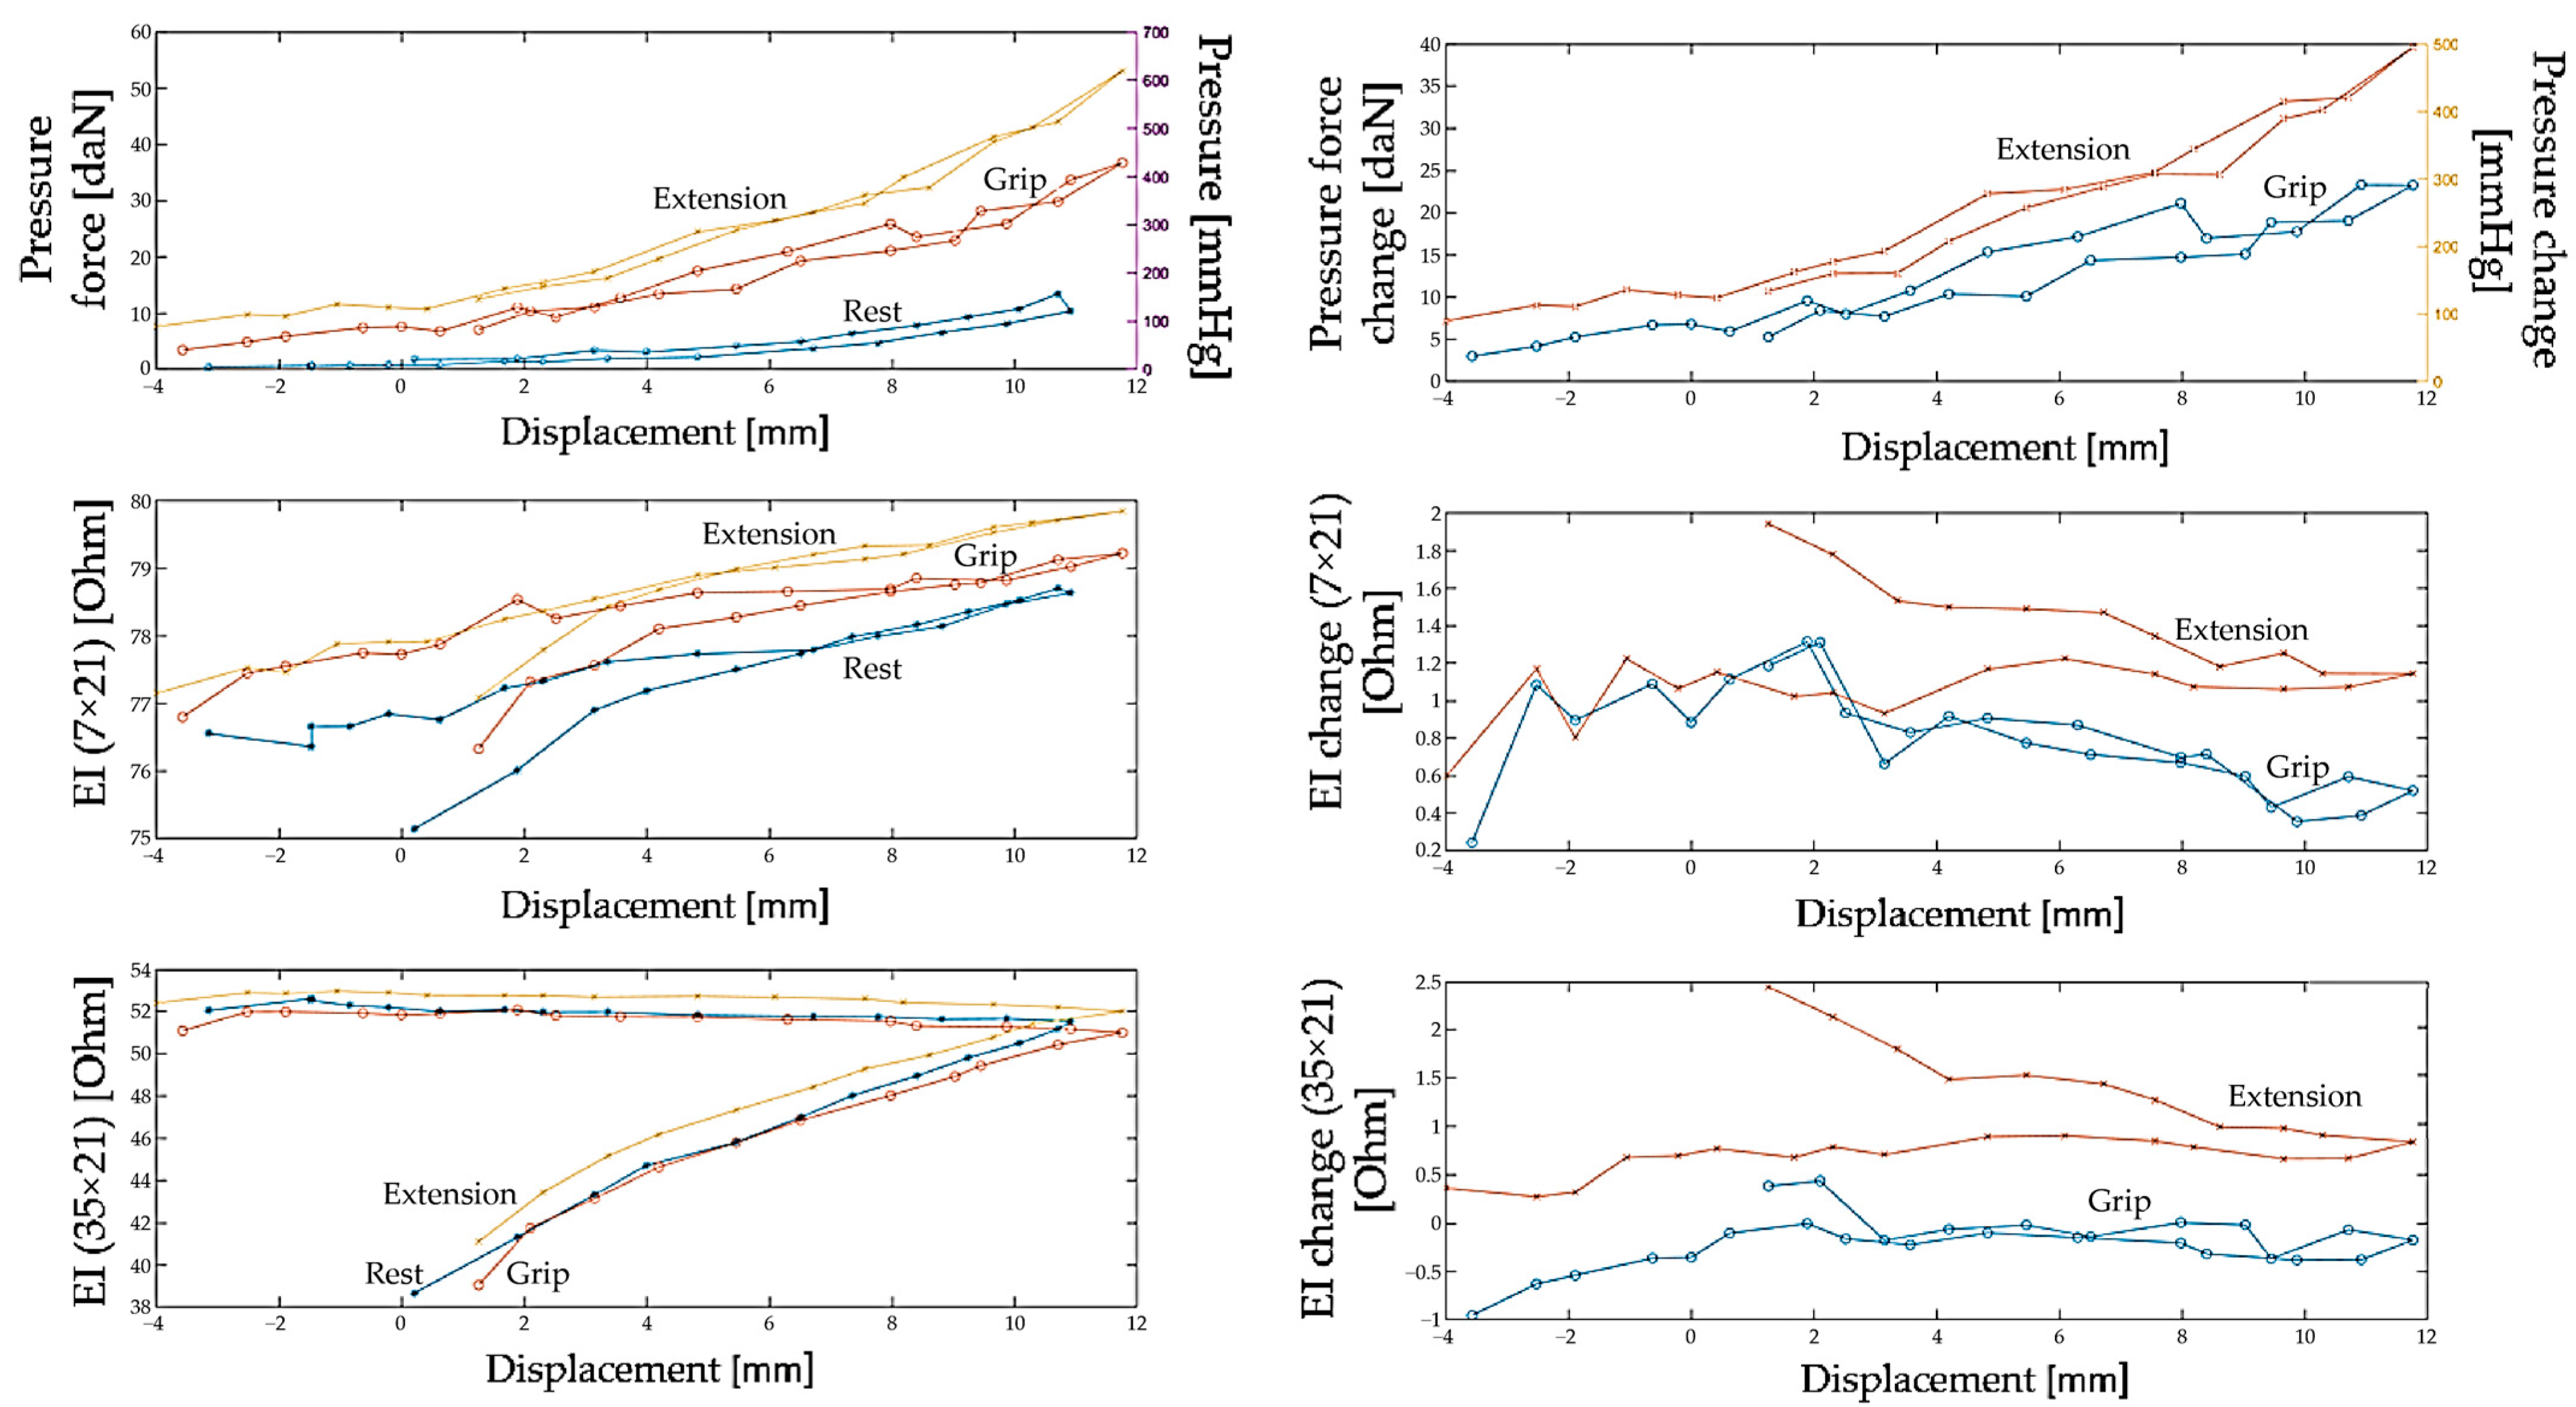

3.1. Study of Morphofunctional Activity of the Forearm Muscles When Performing Actions

3.2. Study of the Amplitude Parameters of the Electrical Impedance Myography Signal at Different Pressures of the Electrode System